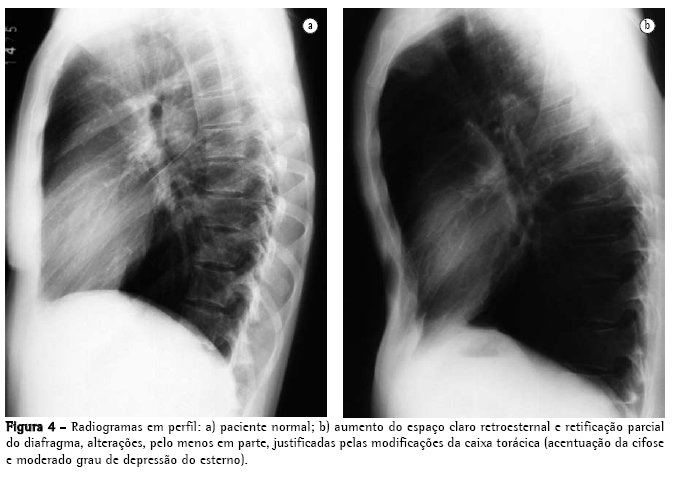

O rendimento do radiograma convencional de tórax na avaliação do enfisema é bastante limitado. Quando ainda não há aprisionamento aéreo significativo, a principal alteração é a redução da vasculatura, que somente é perceptível muito tardiamente na história natural da doença, e é um critério de extrema subjetividade. Quando há aprisionamento aéreo (Figuras 3 e 4), os critérios são mais seguros, podendo ser divididos em 3 grupos básicos de alterações,(6,8) apresentados na Quadro 1. Quando todos os critérios estão presentes, o diagnóstico é de certeza. Deve ser ressaltado que o aumento de câmaras direitas do coração, com redução da vasculatura intra-segmentar, pode também ser identificado em hipertensão arterial pulmonar, sem enfisema. Ressalta-se, também, que bolhas só estarão presentes em cerca de um terço dos casos.

Alguns autores(15) relataram que o comprimento do pulmão direito e a altura do arco do hemidiafragma se correlacionavam bem com o VEF1 e a proporção VEF1/capacidade vital (CV). Neste estudo, um comprimento de pulmão direito de 30 cm ou mais identificou 70% dos pacientes com obstrução respiratória.(16) Entretanto, um autor(17) relata que todos esses estudos apresentam vícios, pois têm excesso de pacientes com obstrução respiratória crônica e, assim, as características radiológicas de obstrução aérea recebem "um valor desproporcional no reconhecimento do enfisema". Também foi demonstrado que a sensibilidade à radiografia de tórax não é boa, variando de 24(18) a 80%(19) e, também, que existe uma considerável variação intraobservadores e inter-observadores, em relação aos sinais radiológicos clássicos.(20) Os sinais radiológicos relacionados à vascularização estão sujeitos a uma variação intra ou inter-observadores ainda maior do que a dos sinais relacionados à hiperinsuflação.(19)

Considerando-se que o hemidiafragma tem superfície de cerca de 250 cm2, pode-se calcular que cada 4 cm de deslocamento do diafragma determina deslocamento equivalente a cerca de 1 L de volume em cada pulmão (2 L, se considerados ambos os pulmões). Quando há aprisionamento de ar, a mobilidade do diafragma está limitada durante a expiração. O volume pulmonar no final da expiração é significativo no reconhecimento do enfisema. Normalmente, o deslocamento do diafragma entre a inspiração e a expiração máximas situa-se entre 3 e 10 cm, correspondendo a volumes de 1500 a 5000 mL. O deslocamento cranial menor que 2 ou 3 cm na expiração é indicativo de limitação da excursão diafragmática no indivíduo com enfisema.(21)

A utilização da altura do diafragma como um indicador diagnóstico é limitada em várias

situações:

nos pacientes com cifoescoliose;

em alguns indivíduos que apresentam diafragma em situação baixa na inspiração, porém preservam uma excelente mobilidade na expiração, como os atletas; e

em indivíduos com asma, especialmente crianças maiores e adolescentes, onde o diafragma pode apresentar algumas das características semelhantes às do diafragma do indivíduo com enfisema, porém as alterações cardiovasculares não estão presentes.

Nas três situações, a excursão diafragmática deve ser maior que a do indivíduo com enfisema.

A utilização da excursão diafragmática também tem limitações, especialmente em: pacientes com insuficiência cardíaca, onde as porções do diafragma que não estão em contato com o coração apresentam maior deslocamento cranial; e pacientes com edema pulmonar, pois a rigidez causada pelo edema pode determinar menor mobilidade do diafragma.